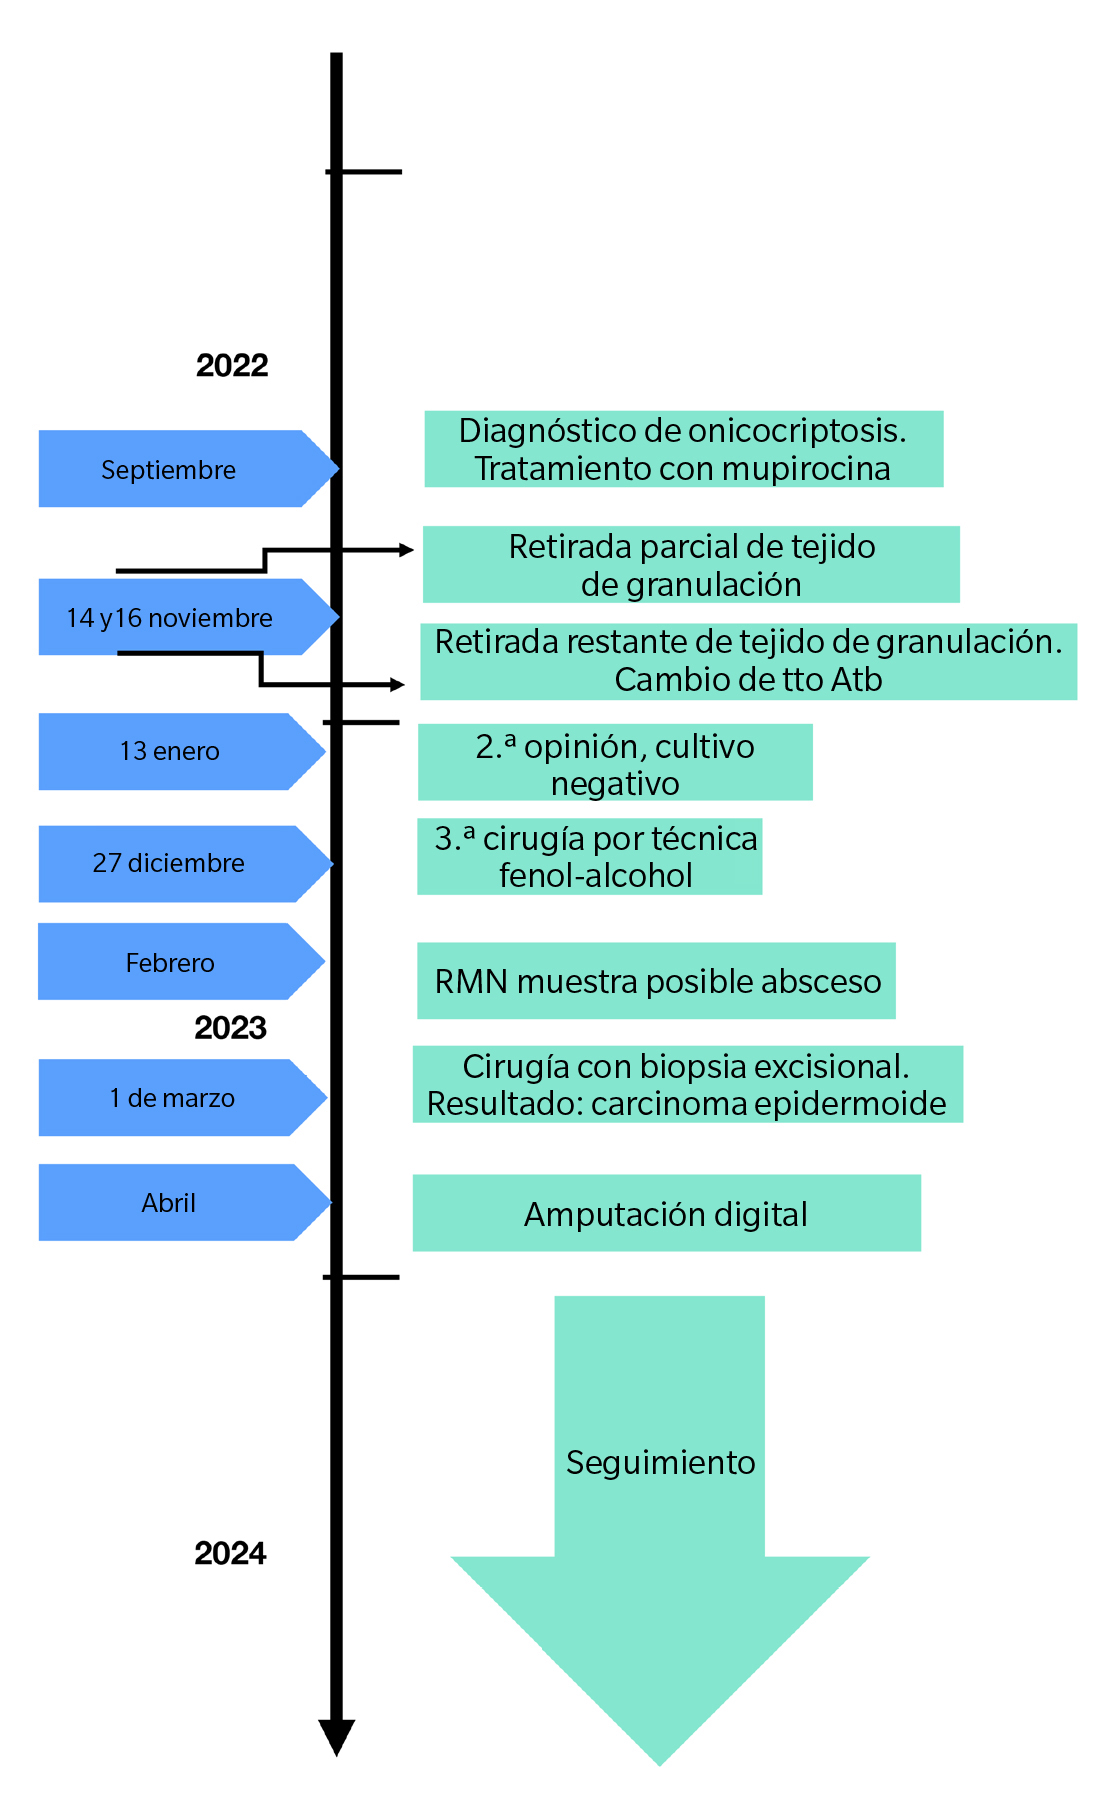

A los 5 días postoperatorios se realizó la primera cura a la paciente, que cursó con buen aspecto y sin infección local. Se explicó el resultado de la anatomía patológica a la paciente y se derivó al servicio de Oncología de su centro hospitalario, y de ahí al servicio de Dermatología y Cirugía plástica donde se realizó la amputación digital (Figura 10). El seguimiento posterior fue llevado por el servicio de Oncología durante los siguientes 6 meses. Después de diferentes pruebas, se determinó que no precisaba otro tratamiento. La Figura 11 muestra la línea de tiempo del caso clínico.

Figura 11. Línea de tiempo del caso clínico.